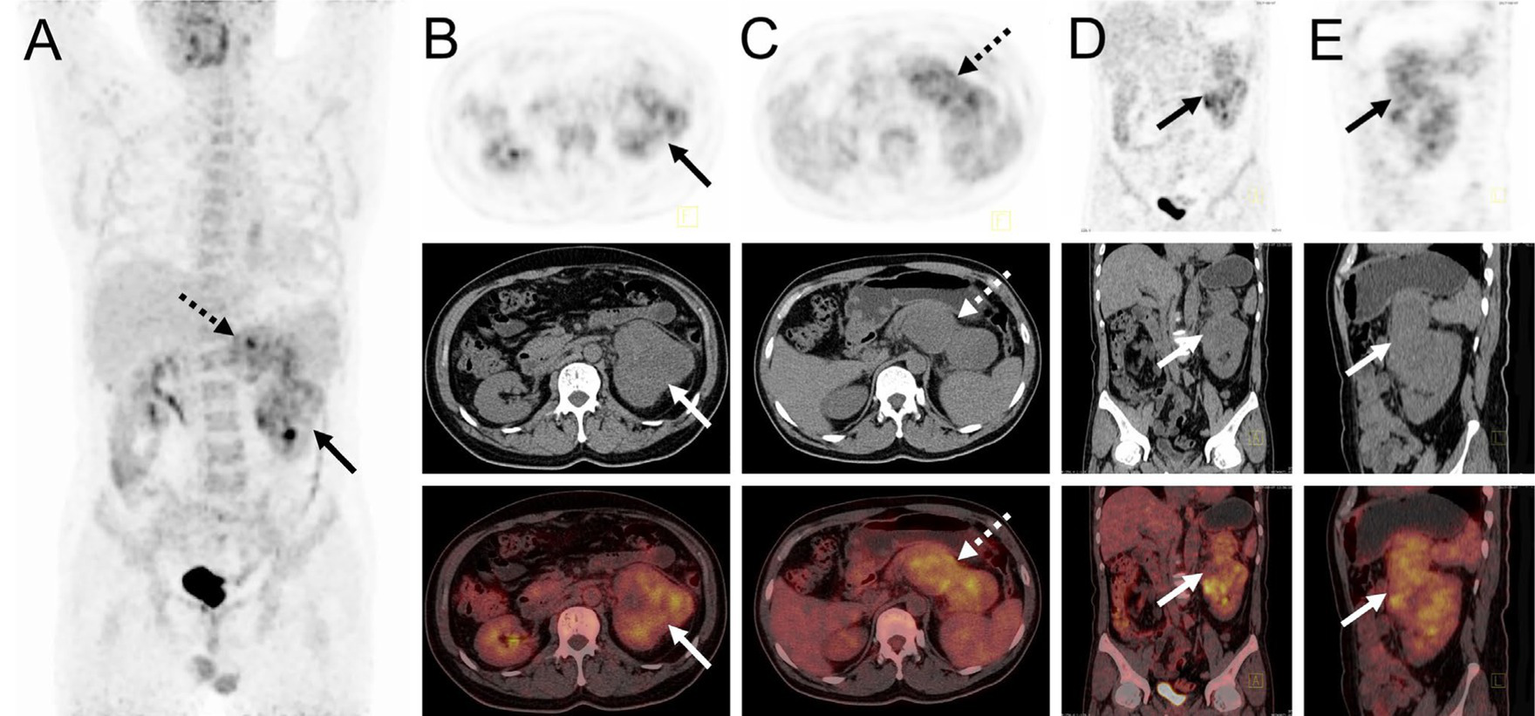

The patient underwent an abdominal ultrasound examination, which revealed a heterogeneous hypoechoic mass in the upper middle part of the left kidney, measuring approximately 7.8 cm × 7.0 cm with unclear boundaries. Color Doppler flow imaging demonstrated grade II blood flow signal within the mass (Figures 1A,B). Additionally, a cystic solid mass measuring approximately 4.8 cm × 4.4 cm was detected in the posterior part of the pancreas, located immediately adjacent to the superior pole of the left kidney (Figures 1C,D). CT examination revealed a heterogeneous hypodense mass in the upper middle part of the left kidney, exhibiting irregular morphology and protrusion towards the exterior of the kidney, along with blurring of the perirenal fat gap. The lesion measured approximately 7.0 cm × 9.0 cm × 10.7 cm, showing significant enhancement (Figure 1E). The mass displayed rich blood supply, with visible branches of the left renal artery entering the mass (Figure 1F). Additionally, a rounded soft tissue density was identified in the pancreatic body. Multiplanar reconstruction revealed a connection between the pancreatic lesion and the mass in the left kidney (Figures 1G,H). 18F-FDG PET/CT was conducted for lesion staging, demonstrating a prominent growth of a lesion in the upper middle part of the left kidney, extending beyond the kidney and infiltrating the pancreatic body. The lesion exhibited significantly high FDG uptake (SUVmax = 10.2, MTV = 136.13 cm3, TLG = 484.62) and had a maximum dimension of approximately 6.8 cm × 8.9 cm (Figure 2).

Figure 2

18F-FDG PET/CT images of myxoid liposarcoma of the left kidney invading the pancreas. (A) The anteroposterior 3-dimensional maximum intensity projection image (MIP) revealed increased metabolic activity in the left kidney (long arrows) and the pancreatic body region (dashed arrows). (B) Transverse images exhibited irregular morphology of the left kidney, accompanied by significantly high FDG uptake (SUVmax = 9.3). (C) Transverse images showed a pancreatic body lesion with significantly high FDG uptake (SUVmax = 10.2). (D,E) Coronal and sagittal images demonstrated an extra-renal protrusion of the left renal lesion and invasion of the pancreas.

The diagnosis of MLS poses an enduring challenge (26). Imaging modalities, including ultrasound, CT, MRI, and PET scans, serve as invaluable tools for tumor identification (32). However, there is currently no established standard regarding the timing and type of imaging surveillance in MLS (9). MLS is distinguished by its distinct pattern of metastatic spread, underscoring the importance of detecting metastatic disease to determine prognosis and guide management decisions (5). In our case, the CT features of MLS included an extra-renal distending, infiltrative growth invading the pancreas with cystic necrosis. Multiple renal artery branches were observed entering the mass, consistent with the pathology of a mucus-like interstitial stroma rich in vascular structures, thereby demonstrating noticeable enhancement. While the presence of fat content is a characteristic feature of MLS, histologically, the mucus component predominates and the fat content is minimal. Consequently, the fat component was not distinctly evident on CT in this particular case. Several studies have documented the substantial clinical efficacy of 18F-FDG PET/CT in the initial diagnosis, staging, biopsy site selection, restaging, and prediction of prognosis and response to therapy in the management of soft tissue sarcomas (33–37). We have summarized the previously reported manifestations of MLS using 18F-FDG PET/CT in Table 1 (19–29), which revealed low 18F-FDG activity ranging from (0.79 to 5.5, median, 2.535). The utility of FDG PET/CT in tumor follow-up has been questioned in some reports (16, 18). However, our case demonstrates a notable 18F-FDG uptake associated with a high-grade pathology (with at least a 10% round cell component), showing increased 18F-FDG uptake by round cells. A unique advantage of 18F-FDG PET/CT was its ability to confirm that the tumor in our case originated from the renal sinus, with direct invasion of the pancreas, thereby excluding the diagnosis of metastatic MLS.